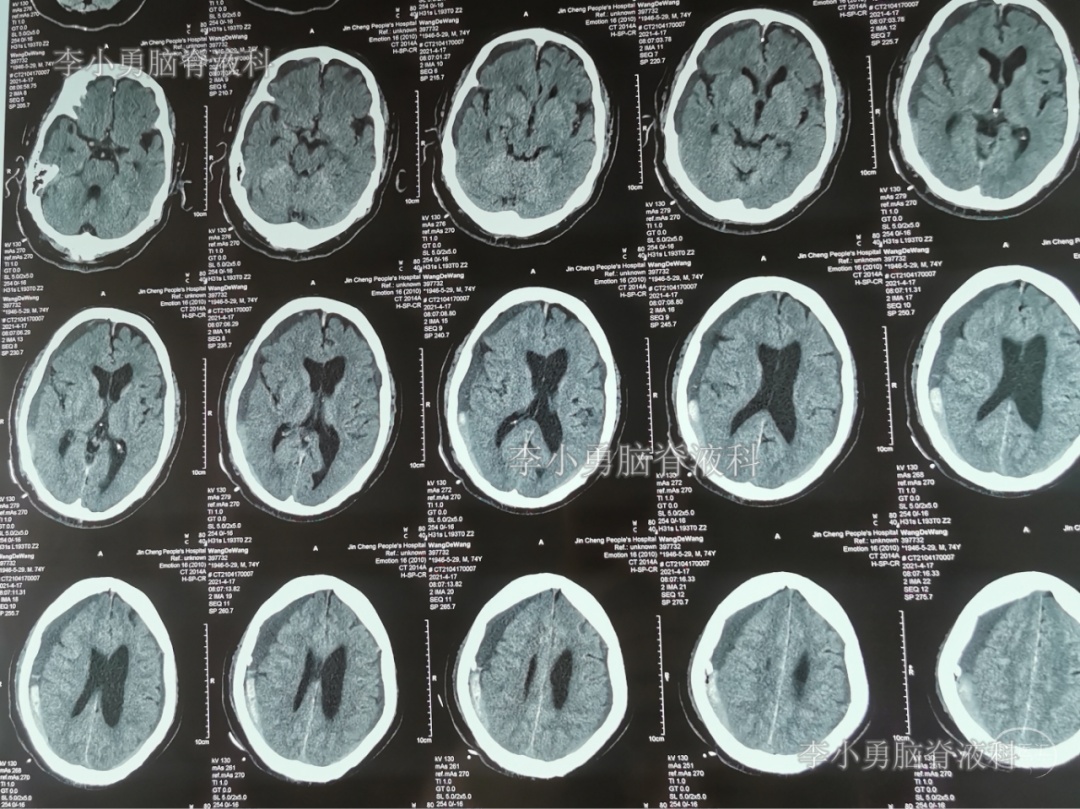

2021年4月14日(腰大池腹腔分流术后17天),头痛腿沉再次加重,复查头部CT示硬膜下血肿(图-3)。

图-3:2021年4月14日头部CT

2021年4月16日(腰大池腹腔分流术后19天),因意识变差,查头部CT(图-4)后,急诊进行了硬膜下血肿引流术,并升高分流泵的压力200。

图-4:2021年4月16日头部CT